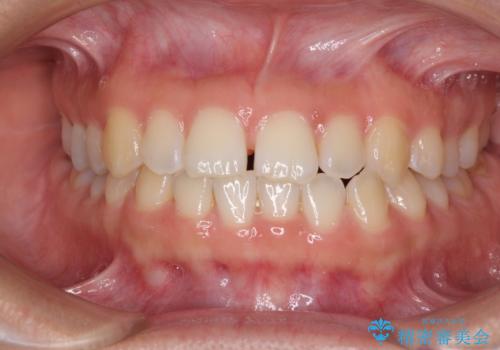

前歯の隙間を閉じたい 短期間でのワイヤー矯正

- 上の前歯の隙間を気にして来院された患者様です。

インビザラインの自己管理は自信がないとのことで、ワイヤー矯正により隙間を閉じていくこととしました。

下の前歯が上の前歯を突き上げるように咬合するため、咬み合わせの位置を改善しながら隙間を閉じていきました。

元々の歯並びが悪くなかったため、9ヶ月で綺麗に仕上がりました。